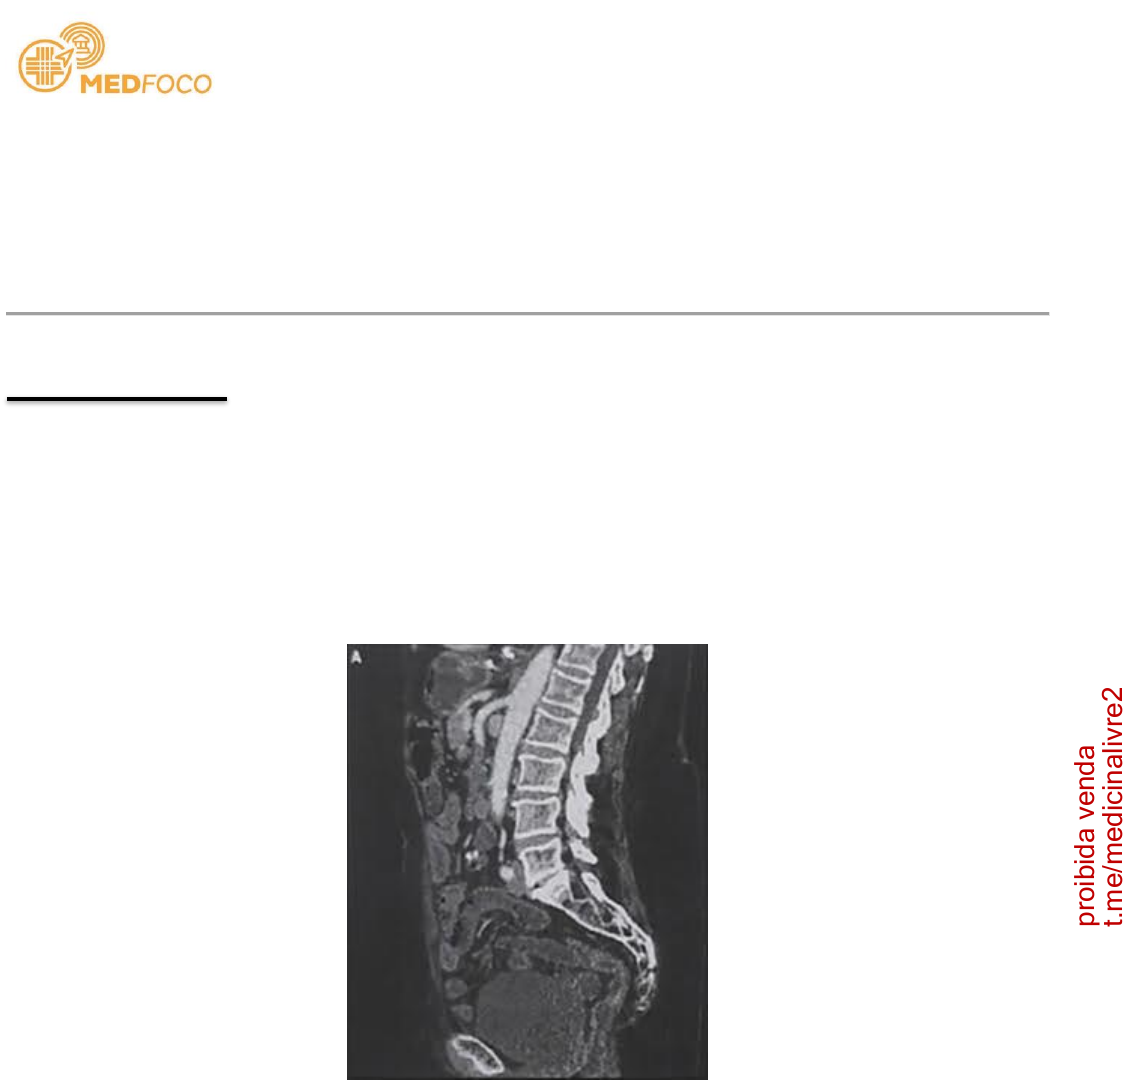

01 - Homem de 65 anos de idade, tabagista de cerca de 40 maços/ano, diabético do tipo II e

hipertenso mal controlado, procura pronto-atendimento por conta de dor abdominal de forte

intensidade de início há 2 horas. O paciente refere que não costuma ir ao médico para

acompanhar a saúde, não toma nenhum medicamento de uso contínuo e sente com frequência uma

batedeira no peito (sic). Ao exame, encontra-se com FC = 105 bpm, PA 155 x 90 mmHg e pulsos

cheios e arrítmicos. Além disso, o abdome encontra-se globoso, flácido e leve dor à palpação

difusa. Foi realizada uma tomografia computadorizada com contraste com o resultado na imagem

abaixo. O médico assistente também solicitou uma gasometria arterial que, apesar de ainda

não estar com o resultado pronto, provavelmente demostrará: